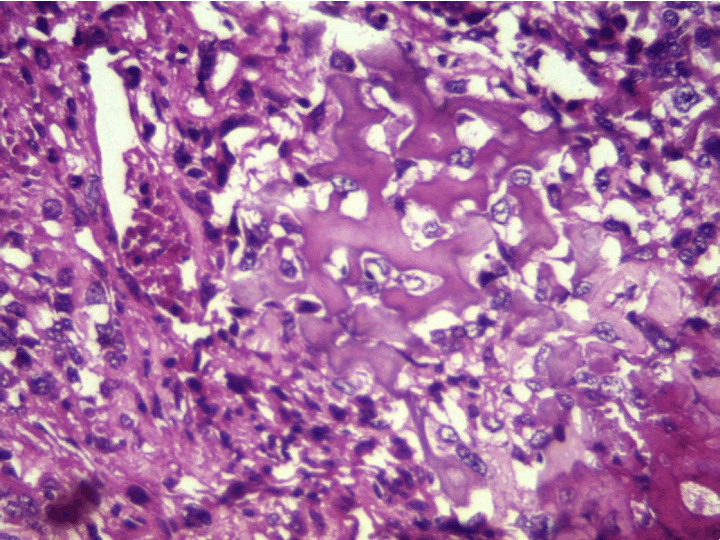

At the pathology laboratory, we received a piece of the left lower limb amputation. (Figure 2) We opened it. Gross examination of the resected distal femur revealed a 22x5 cm intramedullary multicystic hemorrhagic destructive tumor with cortical destruction and extension into the adjacent anterior and posterior soft tissues. The latter component of the mass was larger than the intraosseous tumor. (Figure 3) The articular surface was not involved. We cut the femur in its longest axis with electric saw. (Figure 4) Fixation in 10% neutral buffered formalin for 48 hours and decalcification of bone with nitric acid were performed. Slice of bone section was included in full. Many specimens from soft tissues and the surgical margins were also taken. Microscopic view of histological specimens of tumor stained with hematoxylin andeosin showed prominent blood filled cysts with malignant stroma in septa separating cysts. (Figure 5) (Figure 6) It contained atypical tumor cells oval or round of variable size with osteoblast-like multinucleated giant cells and a variable amount of immature osteoid. (Figure 7) (Figure 8) (Figure 9) (Figure 10) (Figure 11) (Figure 12) Numerous mitotic figures were noted (Figure 13). The tumor was located at 6 cm from the bone limit and 2 cm at the edge of the soft tissues. The resection margins were negative. The marrow, scooped and submitted separately, was negative.

Figure 7: Medium-power view of hemorrhagic area with floating, noncohesive tumor cells, infiltrating trabecular bone (H&E, stain, x100).

Figure 8: Septa shows highly pleomorphic stromal cells and tumor giant cells bordering spaces without endothelial linings. Note minimal osteoid.